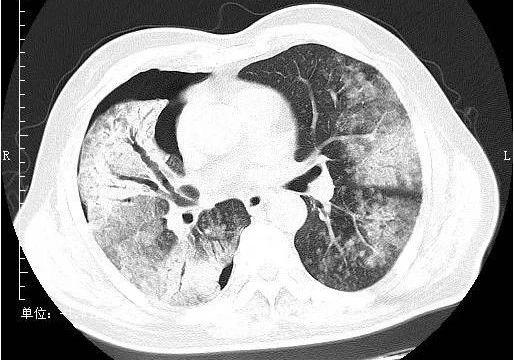

小叶性肺炎(支气管肺炎)

意义: 表明有支气管扩张,慢性支气管炎伴发的细支气管扩张等.

支气管肺炎(在支气管处有阴影,那块状影不是癌)